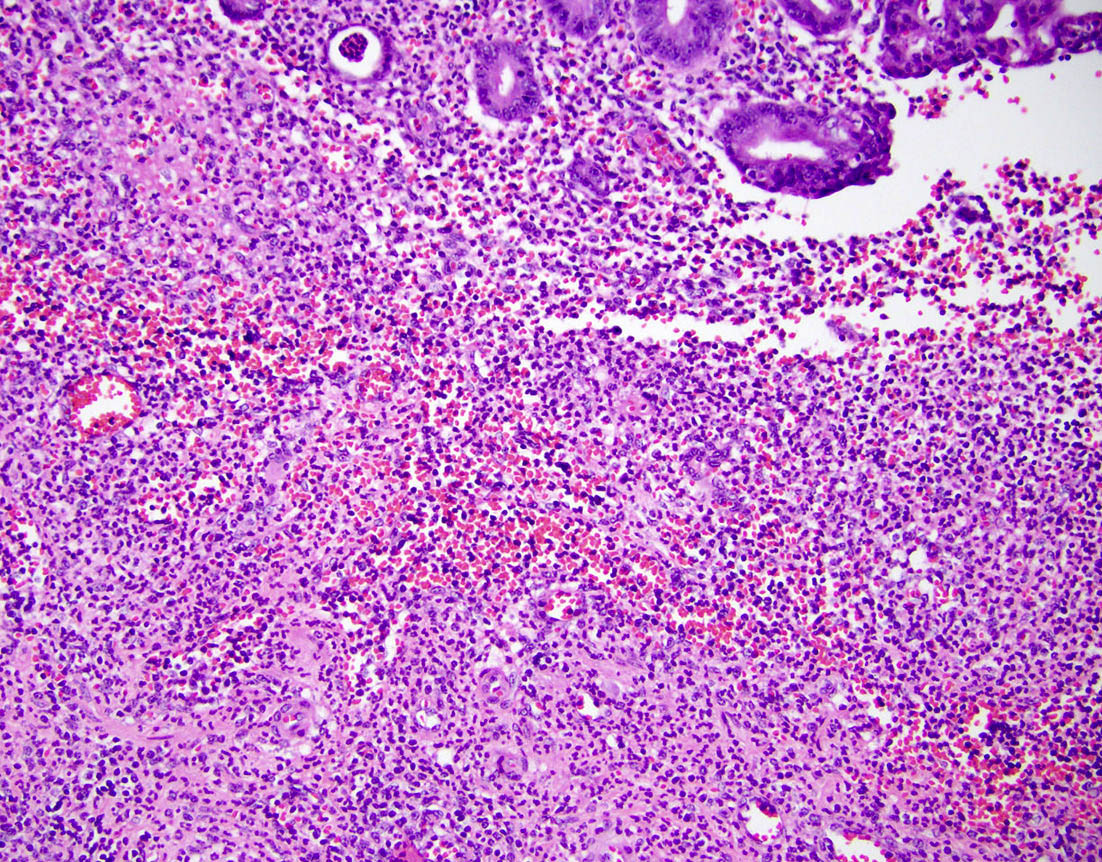

Microscopic (histologic) description

- Variable acute inflammation with predominance of neutrophils; involves some or all layers of the appendiceal wall

- Process may be divided into acute focal, acute suppurative, gangrenous and perforative

- Early lesions display mucosal erosions and scattered crypt abscesses

- Later, the inflammation extends into the lamina propria and collections of neutrophils are also seen in the lumen

Microscopic (histologic) images

- Appendiceal endometriosis:

- Typically has a nonspecific presentation; pain may wax and wane with the menstrual cycle

- Most often affects the serosa or muscularis propria and is accompanied by abundant fibrosis and adhesions

- Microscopically, consists of endometrial type glands and stroma associated hemosiderin deposition and a fibroblastic response (Afr Health Sci 2008;8:196)

A 40 year old caucasian man presented into the emergency room with right lower quadrant pain associated with vomiting, abdominal tenderness, fever and moderate leukocytosis. Acute appendicitis was suspected and he underwent an appendectomy. His appendix was sent to pathology for histological evaluation. The H&E images are shown above. Which of the following is the most likely diagnosis?

A 35 year old woman presented with localized right lower quadrant abdominal pain for 1 day. She also presented with nausea, vomiting, menorrhagia and dizziness. She reported that she was actively menstruating and that these symptoms typically occurred monthly with menstruation but had been particularly severe in that month. CT scan showed thick walled appendix consistent with acute appendicitis. She underwent an appendectomy. The H&E images are shown above. Which of the following is the most likely diagnosis?